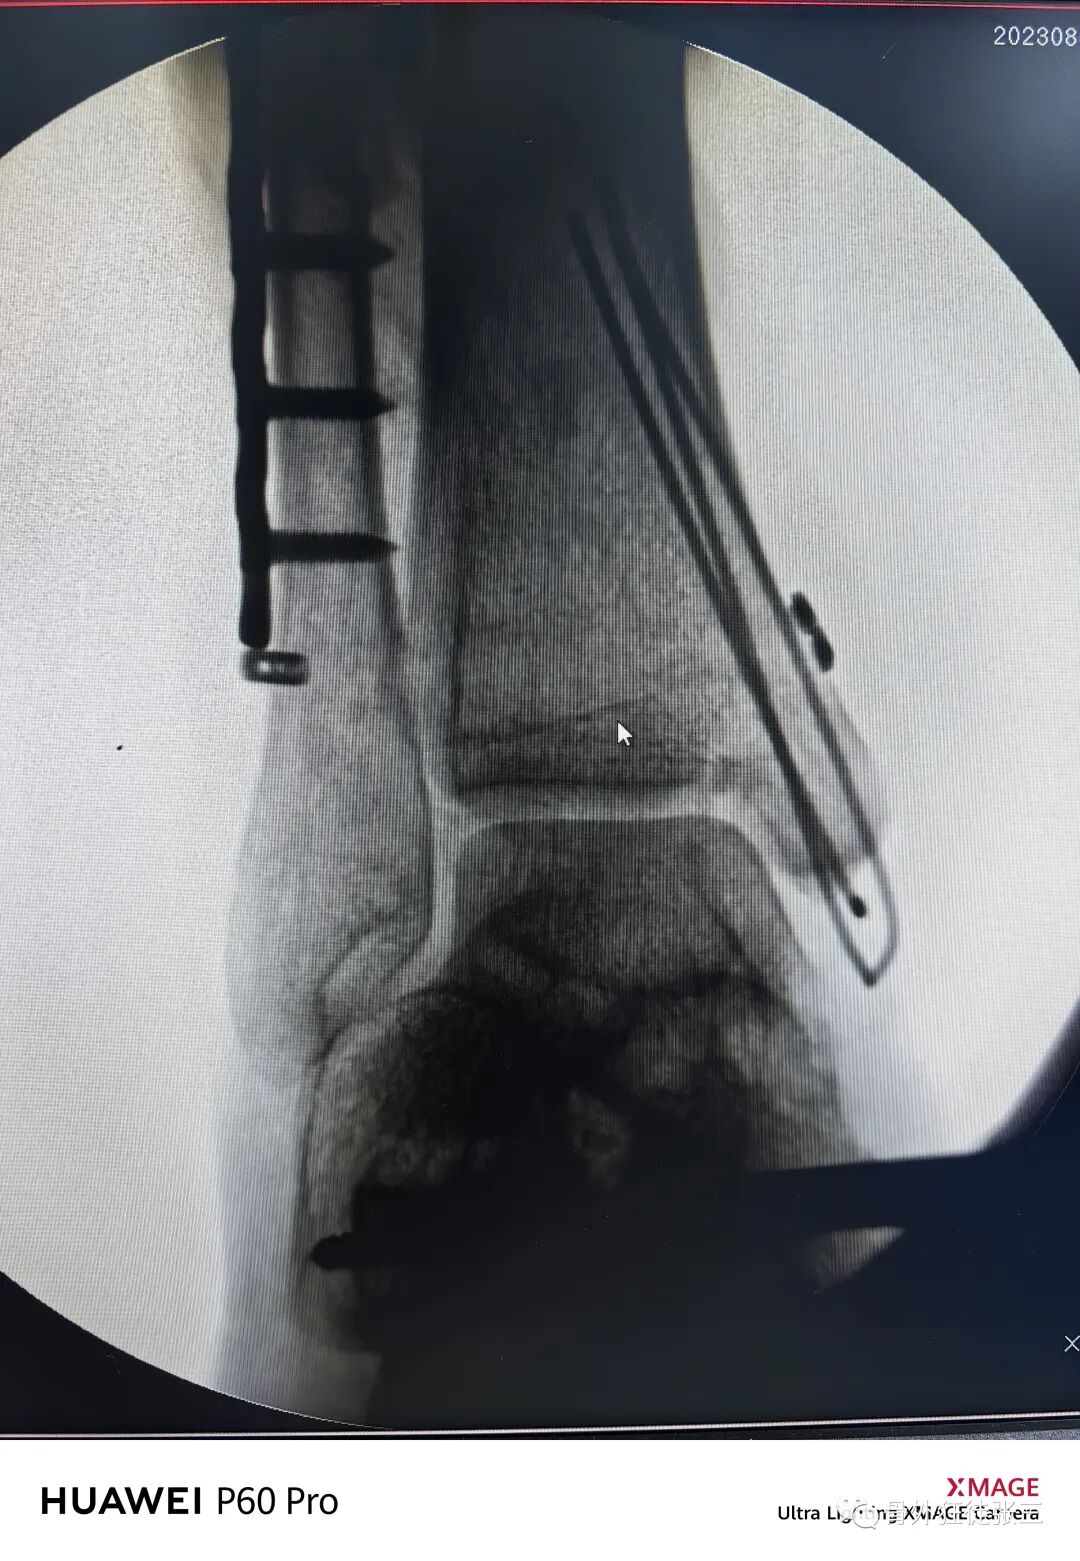

病例28,髌骨骨折,克氏针张力带

病例29,双内踝骨折,克氏针张力带

病例30,股骨干骨折,重建髓内钉,克氏针阻挡针,